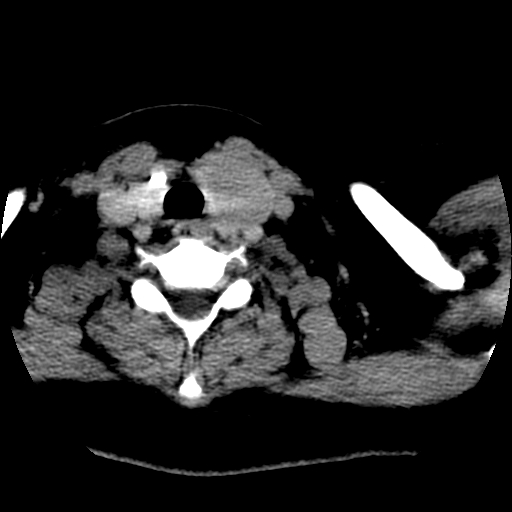

标题: CT25491:女,55岁,发现左侧甲状腺肿块一个月。 [打印本页]

标题: CT25491:女,55岁,发现左侧甲状腺肿块一个月。

女,55岁,发现左侧甲状腺肿块一个月,彩超示:甲状腺多发结节伴左叶结节液化。

左右叶都有,峡部也受累,有钙化,考虑结甲可能性大。

考虑右叶结节性甲状腺肿,伴左叶钙化。主要(1)密度均匀,边境清。(2)病灶与血管界限清。